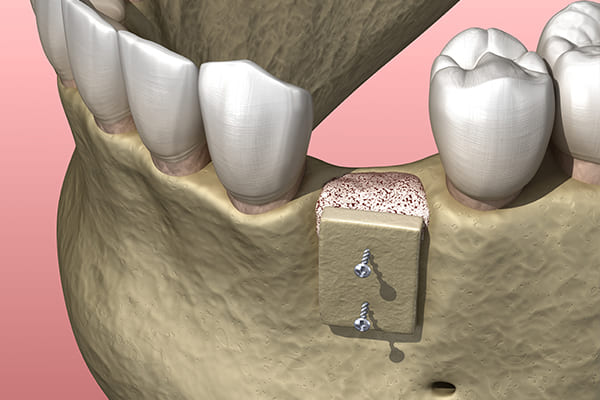

ボーングラフト法

ボーングラフトは、歯槽骨が吸収されて骨の幅が不足し、インプラントを埋入できない症例に適用される骨移植の手法です。

患者様自身の骨を最小限のブロック状に切り出し、骨が足りない部分に移植することで、インプラント治療に必要な骨量を確保します。